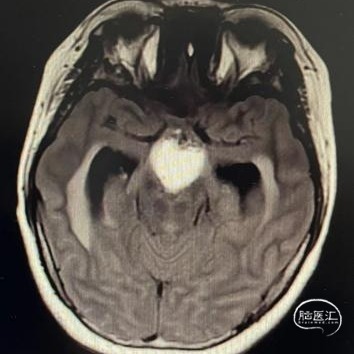

头部MRI显示:鞍区-鞍上区-第三脑室可见一不规则囊状长T1极长T2信号灶,大小约43mm*32mm*43mm,增强后可见病灶不均匀明显强化。垂体及视交叉未见显示,双侧脑室扩张,双侧脑室旁可见对称性斑片状长T1长T2信号灶。